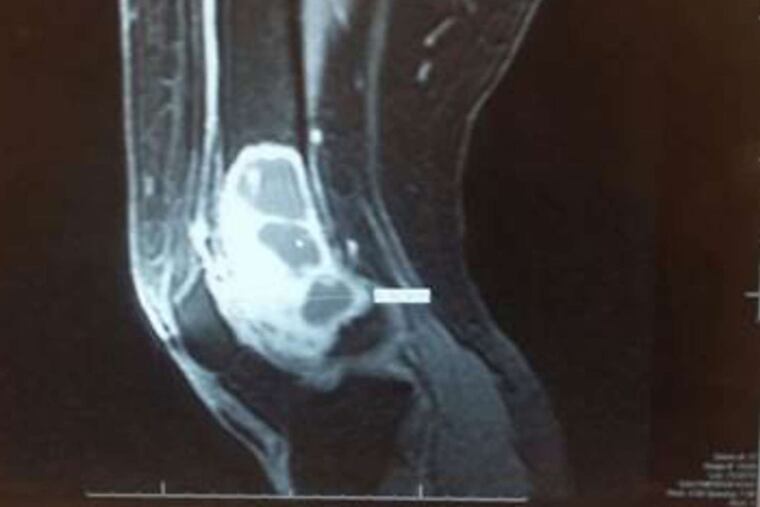

There was an abnormality in the knee. I didn't know exactly what it was, so I ordered a magnetic resonance imaging (MRI) exam. The MRI is a much more sophisticated test. Unlike an X-ray, which primarily shows the bone, the MRI also gives us detailed imaging of the soft tissue, bone marrow, and all the other structures in the leg.

The MRI results confirmed my suspicions that Annette had a much bigger problem than simply a fractured bone.

I reviewed her records and could immediately see the tumor in her leg. I ordered a new set images focused on the abnormality in her knee, to see whether any changes had occurred. We performed a biopsy of her bone at our Bone and Soft Tissue Tumor Center.

The biopsy confirmed my suspicions: She had a giant cell tumor of the bone, a rare, aggressive tumor that is not cancerous, but still tends to destroy the bone.